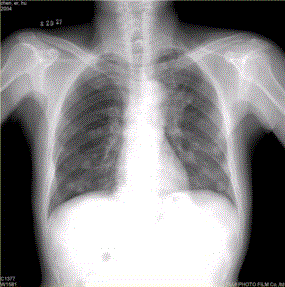

问题 患者男,45岁,因肝硬化、肝癌行肝移植术后6个月,咳嗽2周,来院复查。CR及CT影像如下图。 对于该病例,首选诊断为

选项 A.肺结核 B.肺转移瘤 C.肉芽肿性疾病 D.支气管肺泡癌 E.淋巴瘤 F.支气管肺癌

答案 B

解析 B